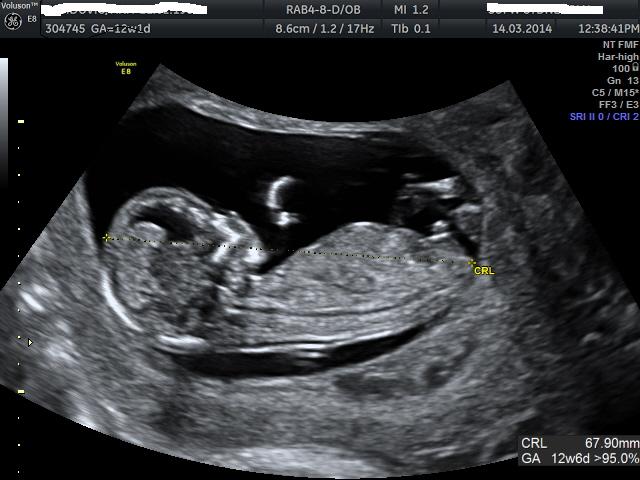

12weeks + 6 days

Definitely boy! Congrats!

Boy!

Wow definitely boy....perfect boy nub there!! Congrats x